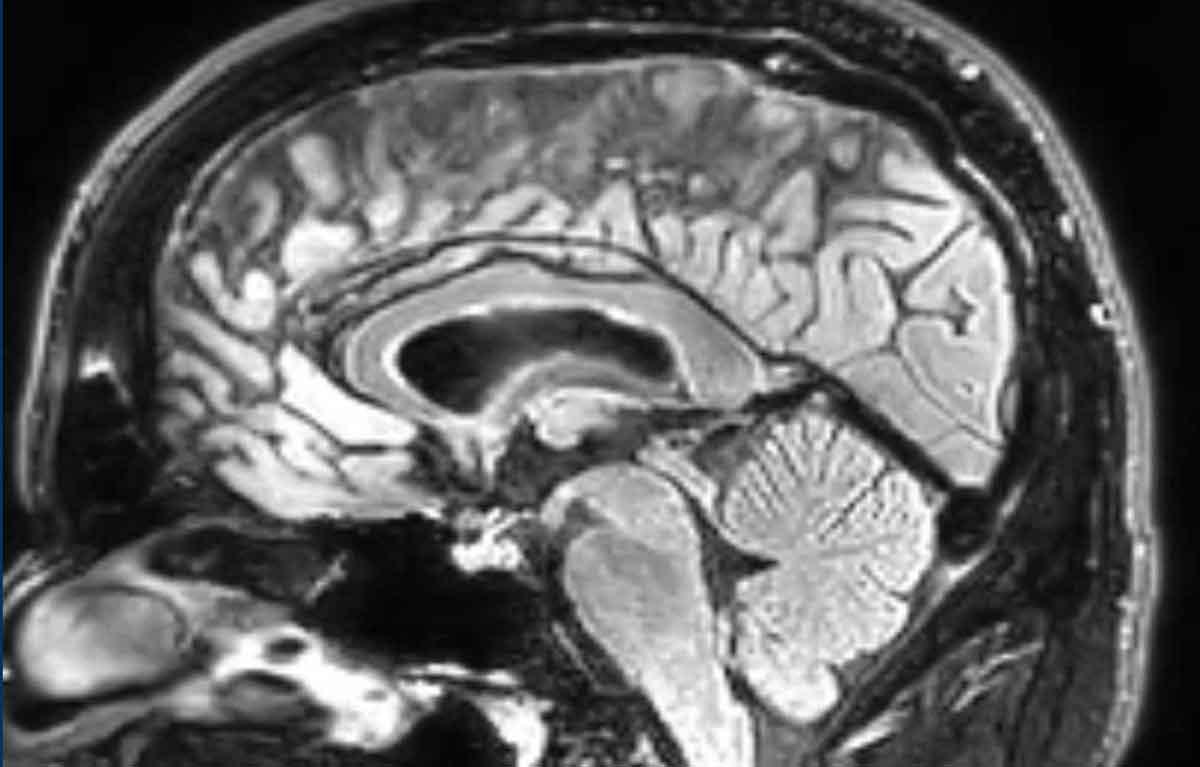

Hình ảnh này của một bệnh nhân có triệu chứng đau đầu.

Chuỗi xung FLAIR cho thấy các đặc điểm điển hình của hạ áp nội sọ tự phát:

- Giãn tĩnh mạch và xoang tĩnh mạch màng cứng

- Trung não bị võng xuống mức độ nhẹ

- Giảm khoảng cách thể vú – cầu não

Tiếp tục xem MRI và chụp tủy đồ CT…